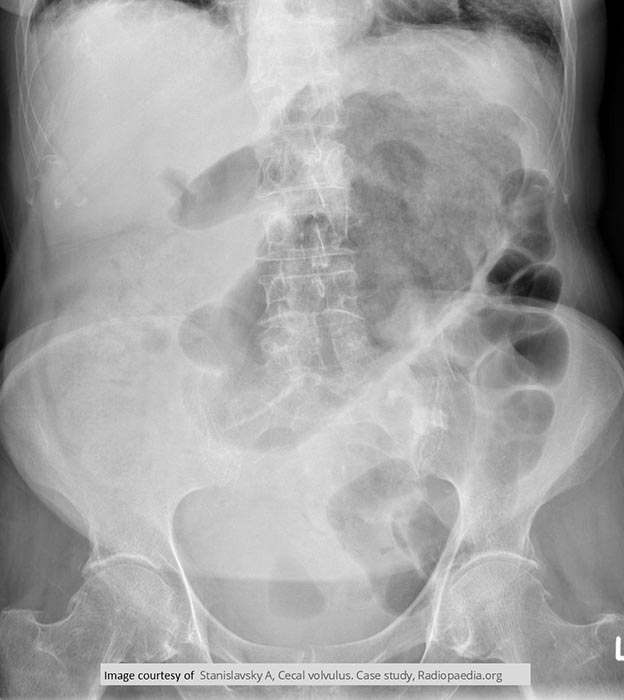

Where does volvulus most commonly occur?

In the cecum and sigmoid colon. (image shows cecal volvulvus)

Which age group commonly experiences cecal volvulus?

Younger individuals.

How does cecal volvulus occur?

The cecum twists on its long axis and often displaces upward and to the left.